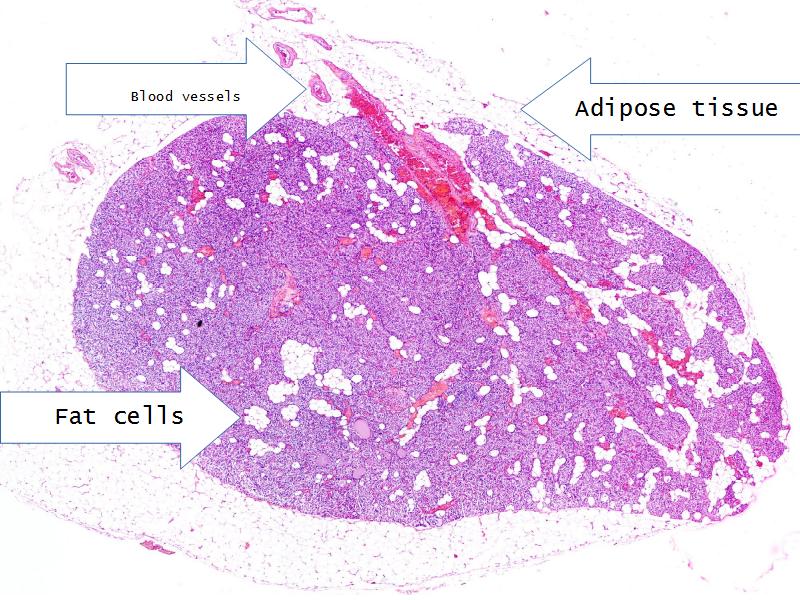

- Parathyroid glands

- Slide 54: Parathyroid glands

Chief cells = majority

Oxyphil (acidophil) = single/groups